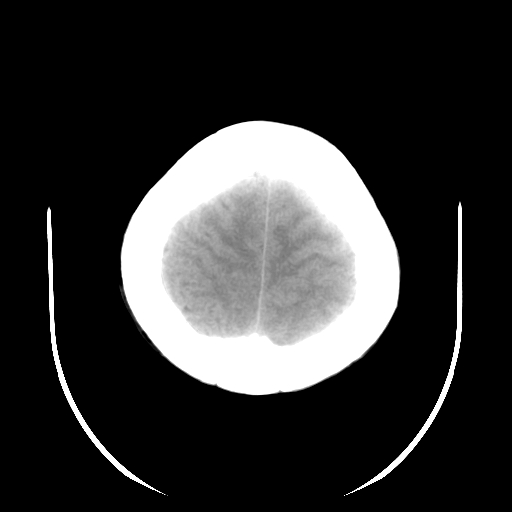

标题: CT19189:女,38岁,右侧肢体偏瘫、失语5天。 [打印本页]

女,38岁,右侧肢体偏瘫、失语5天,发病1小时曾在外院做头颅ct检查未见异常。

窗宽窗位没调好。

两个稍高等密度灶,有占位性,广泛白质水肿,建议除外肿瘤检查

考虑肿瘤性脑出血(胶质母细胞瘤)伴灶周水肿可能性大。38岁人暂不考虑出血性脑梗塞。